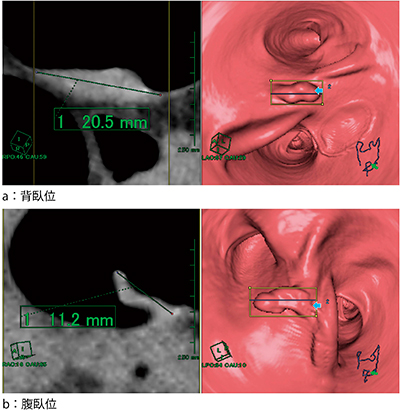

5.2体位比較読影でのポリープ断面観察(図4)

従来,2体位比較では行えなかったポリープ断面観察が2体位比較で可能となり,非常に有益となった。

図4 2体位比較読影でのポリープ断面観察

6.2体位比較読影の仮想内視鏡画像で現在位置からカットMPR断面表示(図5)

従来,仮想内視鏡MPR表示においては表面からの距離でMPR断面を表示していたが,今回,仮想内視鏡画像の現在位置からのMPR断面表示が可能となった。仮想内視鏡MPR表示は,径が一定で観察画面から断面表示が消えなくなり,解析中に断面位置の変更が不要となった。

図5 2体位比較読影における仮想内視鏡MPR断面表示

仮想内視鏡MPR断面が現在位置からカットが可能となった。